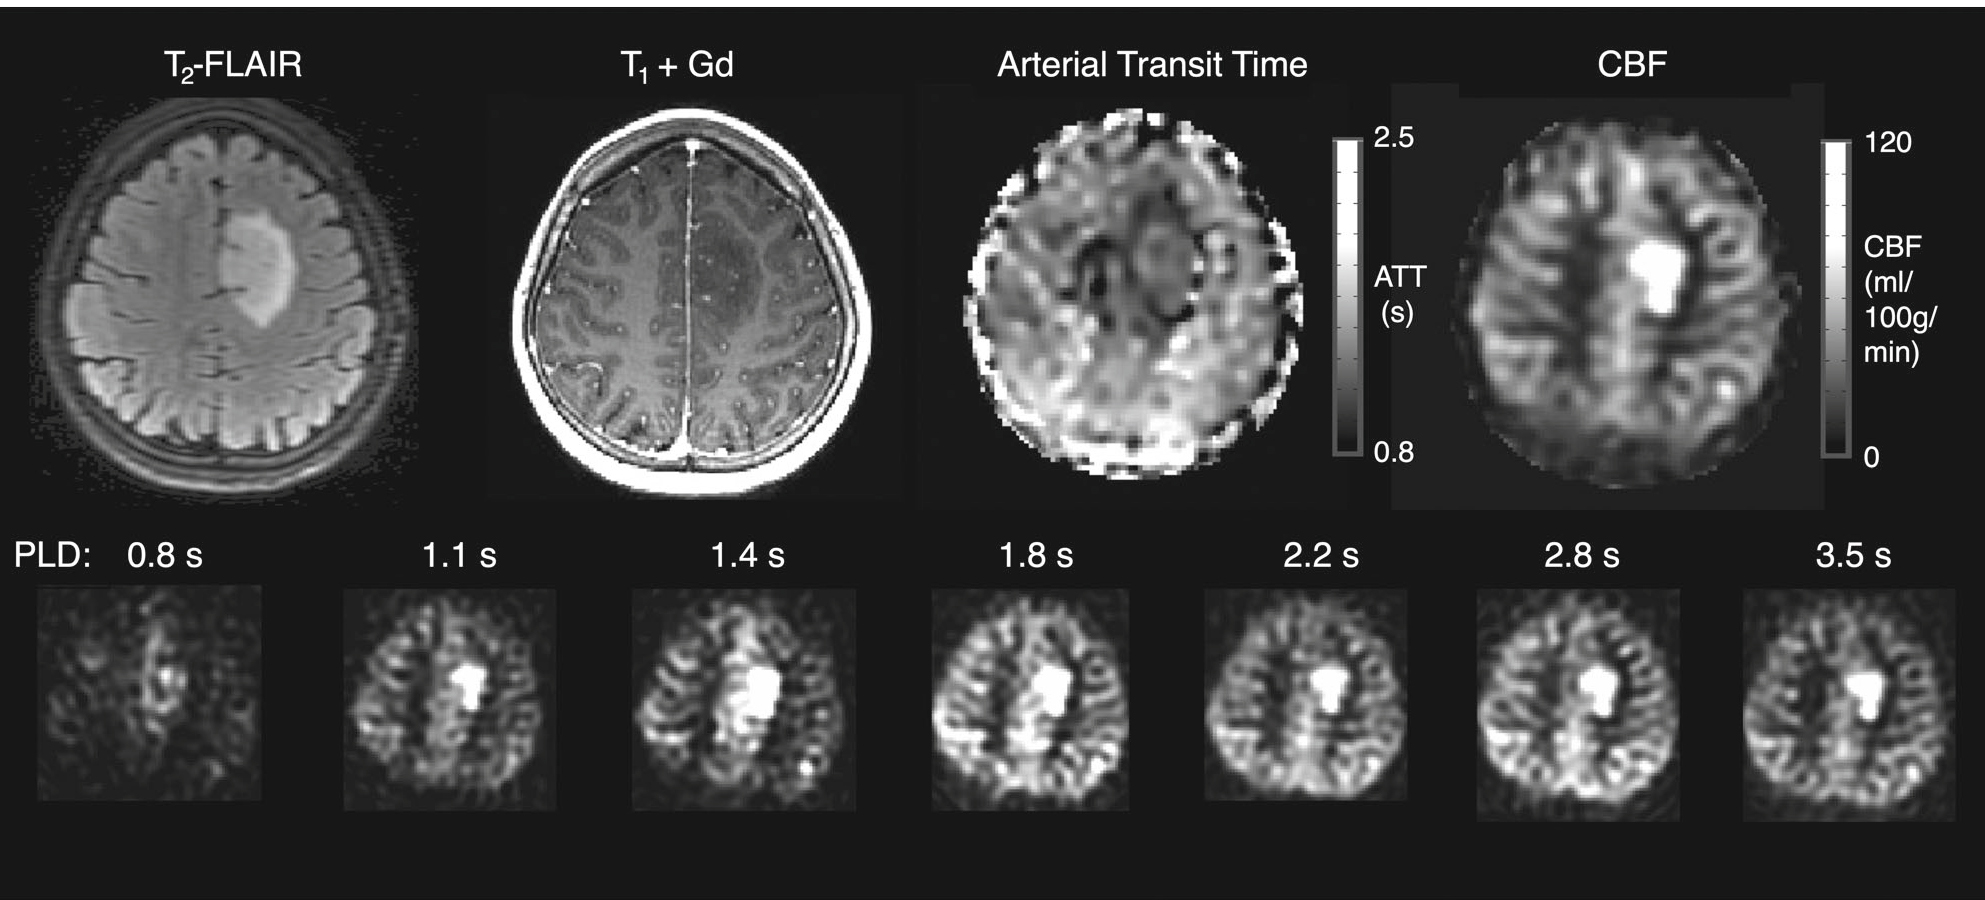

动脉自旋标记(ASL)成像在临床上被广泛用于辅助诊断脑肿瘤及监测治疗效果,区分肿瘤复发与治疗效应。多时间点ASL技术通过提供更精确的脑血流量(CBF)测量,有助于表征肿瘤血管的不规则性,从而改善术前肿瘤分级和治疗反应评估。研究表明,多时间点ASL能够区分不同级别的星形细胞瘤,而传统单PLD ASL则不能。此外,多时间点ASL在增强肿瘤中,尤其是在DSC测量受限于血管渗漏时,能提供更深入的微血管灌注信息。因此,推荐在未来的肿瘤学研究中采用多时间点ASL,以进一步探索肿瘤血流特性。图7示例展示了低级别弥漫性胶质瘤(少突胶质瘤,WHO 2级)中多时间点PCASL成像的结果,包括T2-FLAIR上的肿瘤高信号区域,未增强的T+Gd图像,以及计算得到的PCASL CBF和ATT图,这些图像揭示了肿瘤区域内的高灌注和短到达时间区域。

7d7eb96211adfce52a7c81e609d8dabd.jpg

图7:一个在低级别弥漫性胶质瘤(少突胶质细胞瘤,WHO2级)中进行时间编码的多时间点PCASL采集的例子。最上面一行:肿瘤范围见T2区(高信号区)。T+Gd没有增强。计算出的PCASL CBF和ATT图显示,肿瘤区域内有一个高灌注区域,到达时间较短,部分原因是该数据中存在大量的血管内信号贡献,而这里没有建模。这与少突胶质细胞瘤倾向于高度灌注、具有高血容量、不规则但无渗漏的血管系统的发现是一致的。最下面一行:在每个获得的pld上的灌注加权图像。